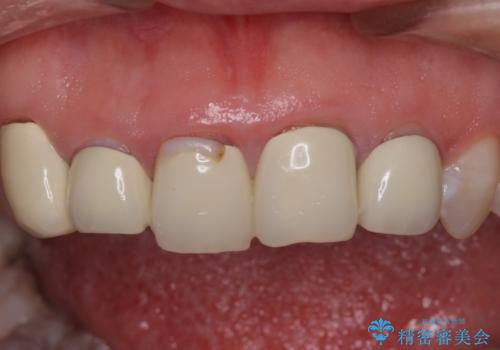

- 歯列不正を改善する目的で装着した前歯のセラミックが気になるとのことで来院された患者様です。

金属の裏打ちを用いたセラミッククラウンであったため歯肉縁に黒ずみが見えてくることは良くありますが、全体的に歯列が不揃いであることが気になったので、それらをオールセラミッククラウンにて改善することとしました。

セラミッククラウンが外れてしまうことを心配して、歯ブラシをあまり当てられなかったとのことで、歯肉に軽度の炎症が認められました。